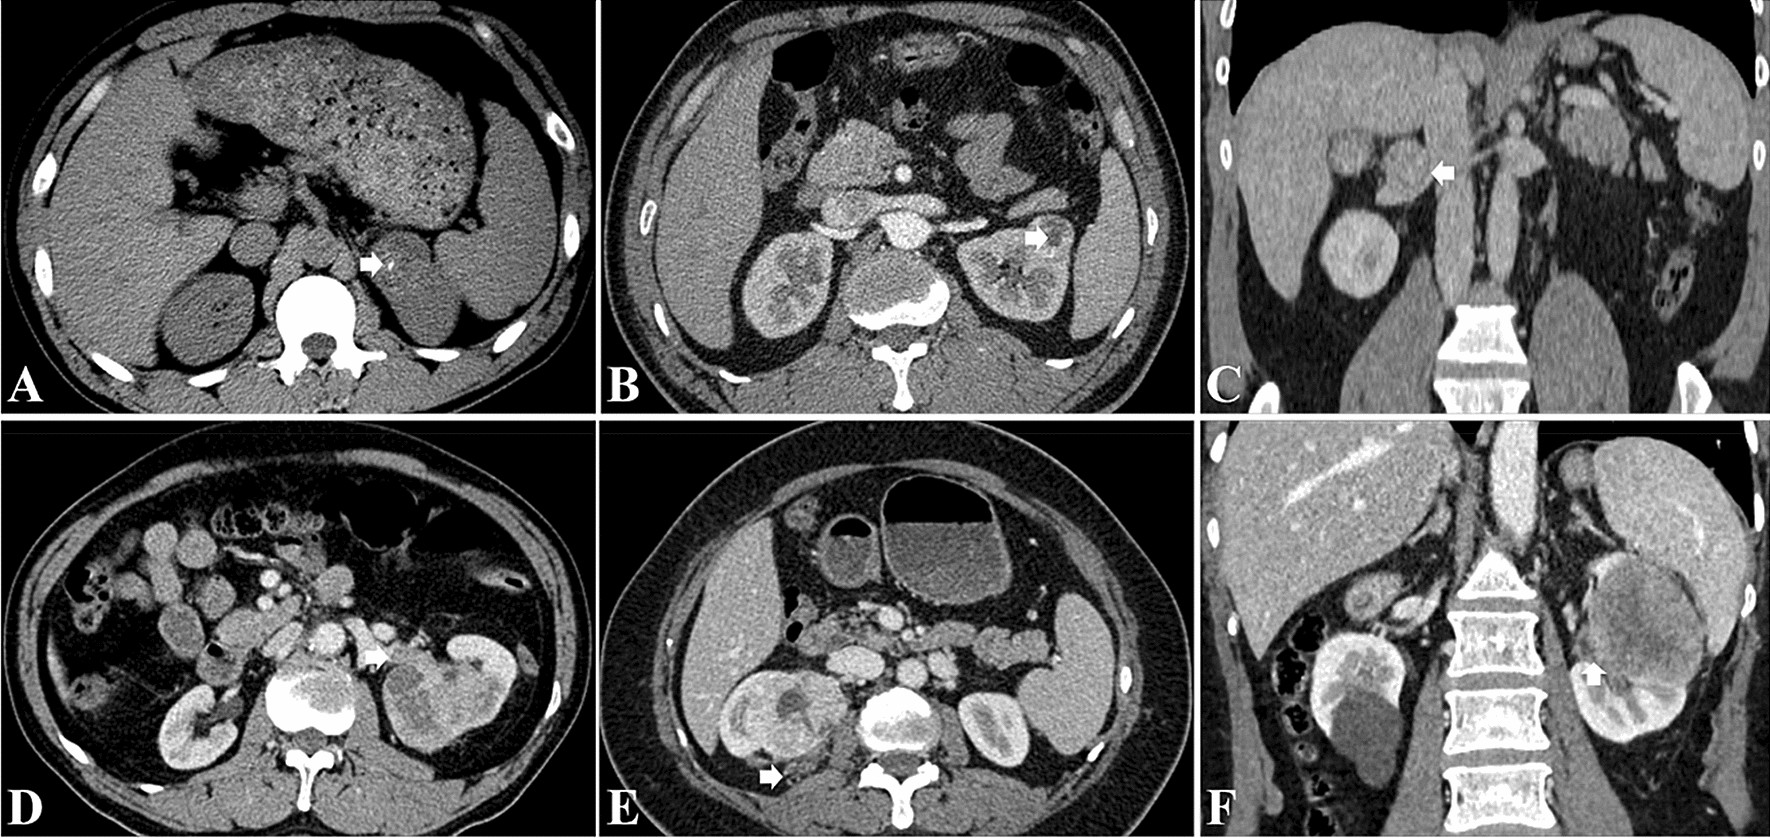

Figure 3

CT imaging features as assessed by both readers: (A) calcification; (B) necrosis; (C) renal vein invasion; (D) renal vein thrombus; (E), perirenal fat invasion; (F) renal sinus invasion.